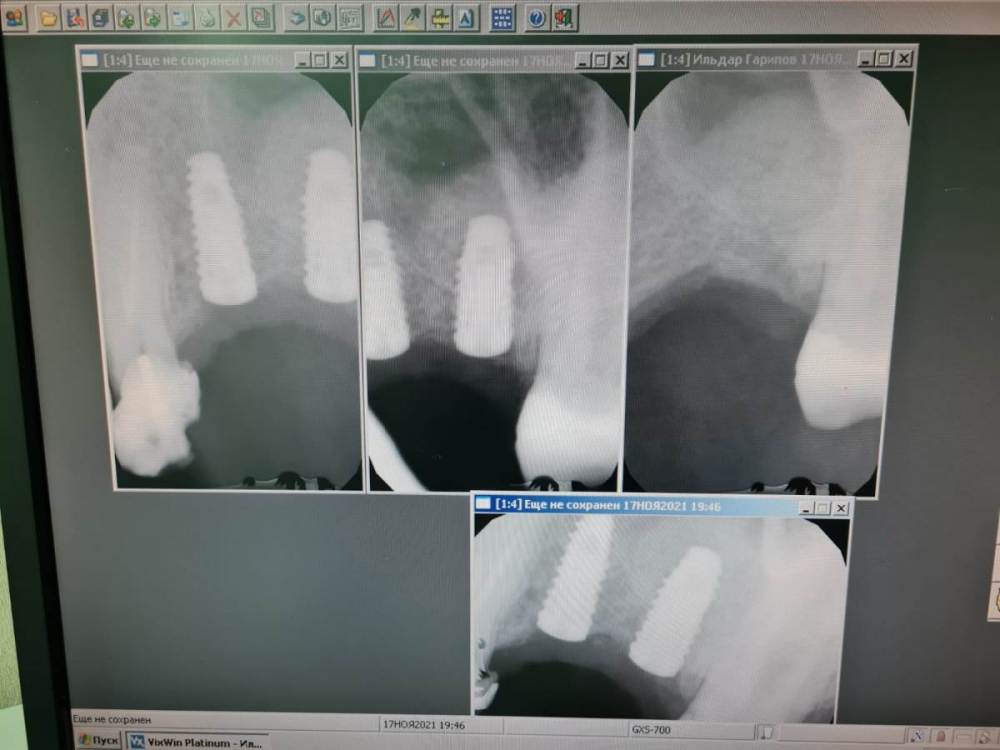

ДокторБро Опубликовано 19 ноября, 2021 Автор Поделиться Опубликовано 19 ноября, 2021 (изменено) Пока так. К сожалению, в клинике нет КТ. Доступ через гребень. На деле оказалось 2мм кости. Будем ждать. Изменено 19 ноября, 2021 пользователем ДокторБро Ссылка на комментарий